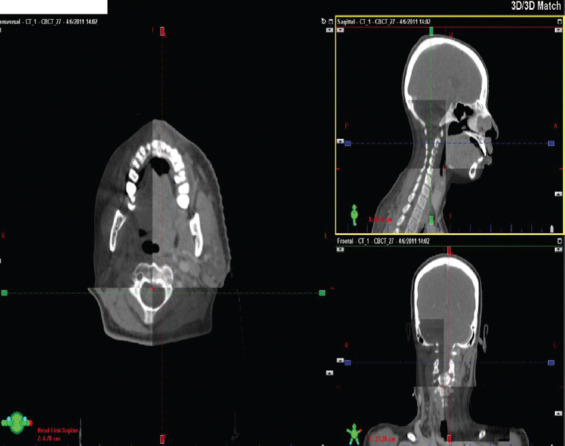

In this study, we assessed the precision and repeatability of the daily patient positioning for three distinct immobilization devices used for head-and-neck patients undergoing RapidArc radiation therapy using cone beam computed tomography (CBCT). An analysis was conducted on the accuracy of patient setup for three distinct immobilization devices, resulting in 1204 CBCT images for 189 patients in total. Using a typical posifix supine headrest and five fixation point podcast-plus-thermoplastic masks, the first group of 39 patients (125 CBCTs) was immobilized. The identical method was used to immobilize the second group of 19 patients (158 CBCTs) in the same posture (supine), and AccuFormTM custom headrests were employed as an added measure. Over 65% of the patients in the third group had a double shell positioning system (DSPS) covering their entire head and neck. Patient-alignment-accuracy or couch shifts in the vertical, longitudinal, and lateral directions from CT-CBCT fusions were recorded from ARIA. Our results showed that in 90% of the anteriorposterior (AP), 90% of the superior-inferior (SI), and 92.7% of the right-left (RL) population in the first group, patient-alignment-accuracy or couch shifts were within 2 mm. For 99.4% (AP), 100% (SI), and 98.7% (RL) of the second group's total population, patient-alignment-accuracy was within 2 mm. In the third group, it was within 2 mm for 92.1% (AP), ~89% (SI), and 93.3% (RL) of the total population. In conclusion, a significant improvement was seen with the application of a mouth bite and a tailored backrest cushion to the five fixation point posicast mask. In addition, significant improvement in the alignment of the lower neck area was observed with the use of DSPS. Virtually 100% of the head-and-neck patients were aligned within an accuracy of 3 mm, which is the PTV margin in our department.

Abstract Image